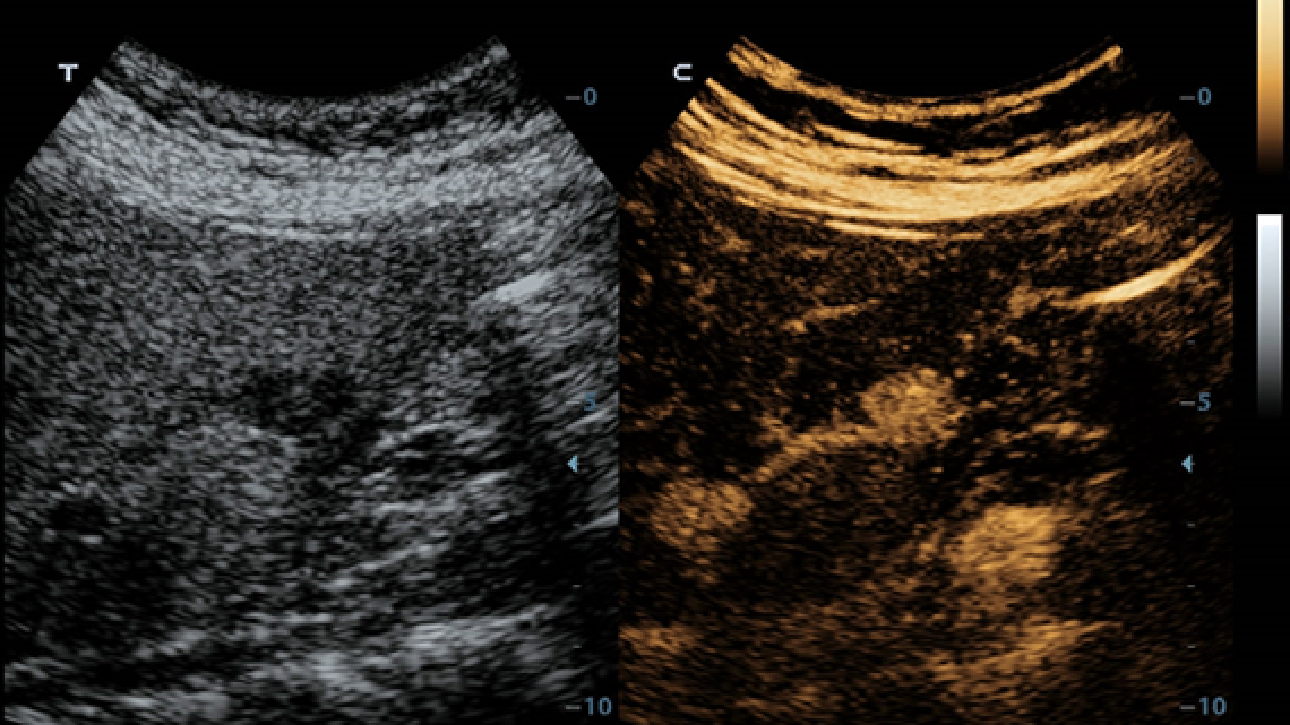

X-Insight es la soluci├│n intuitiva para una mejor visualizaci├│n.

La nueva soluci├│n de Mindray es una excelente transformaci├│n desde la continua comprensi├│n de las necesidades cl├Łnicas del usuario, combinada con la evoluci├│n de la tecnolog├Ła de los ultrasonidos m├Īs puntera. Repleto de vitalidad, con el ├║nico objetivo de visualizar el futuro y evitar los l├Łmites, el ec├│grafo DC-60Exp con X-Insight est├Ī constantemente mejorando con una escalabilidad aumentada. Como un socio personal, el equipo de ultrasonidos DC-60 Exp con X-Insight se centra en lo que verdaderamente importa, ayudando al usuario a administrar su pr├Īctica cl├Łnica con facilidad y seguridad.

Bas├Īndose en una profunda comprensi├│n de las necesidades del usuario, el sistema de ultrasonidos DC-60 Exp con X-Insight est├Ī dise?ado para ofrecer una alta eficiencia con im├Īgenes de precisi├│n, la cual se ve potenciada por una claridad inmediata, una inteligencia excepcional y benefici├Īndose de una c├│moda experiencia.